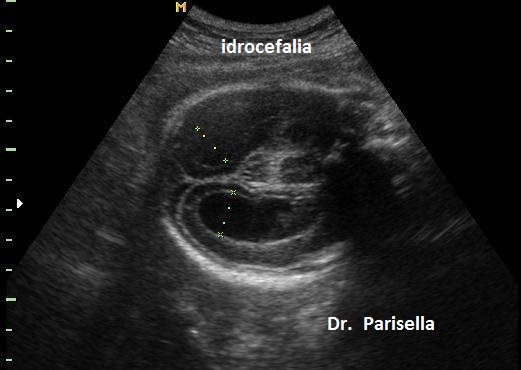

- il tipo I caratterizzata da placentomegalia ad aspetto multicistico, normosviluppo fetale e set cromosomico aggiunto di origine paterna (la dispermia è la causa più frequente di triploidia), micrognazia, anomalie del SNC (idrocefalia), cardiopatie, igroma cistico, oligoamnios.

- il tipo II caratterizzata da una placenta piccola, IUGR, set cromosomico aggiunto di origine materna (diginia), micrognazia, anomalie del SNC (idrocefalia), cardiopatie, igroma cistico, oligoamnios.